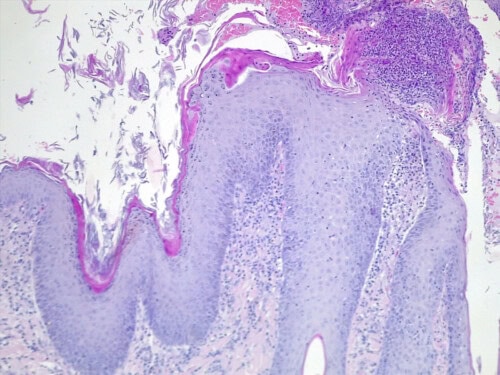

Un examen histopathologique est demandé au LAPVSO (Dr Frédérique DEGORCE). Les biopsies mettent en évidence des lésions surélevées focales en plaques, caractérisées par une une hyperplasie psoriasiforme, épidermique, avec spongiose, œdème des acanthocytes et une forte exocytose de granulocytes neutrophiles, évoluant en pustules granulocytaires sous et intra-cornées qui s’impétiginisent. Dans le derme sous-jacent un infiltrat forme une plage cellulaire d’allure lichénoïde, les cellules se collectant sous la membrane basale épidermique et entourant les apex folliculaires. L’infiltrat cellulaire est formé de granulocytes neutrophiles, de cellules histiocytoïdes et petits lymphocytes et de plasmocytes. Une vésiculation hydropique est présente à l’interface des structures épithéliales ainsi que quelques corps apoptotiques dans leur couche basale. Aucun élément figuré, ni parasitaire, ni fongique n’a été détecté sur les différents plans de section effectués, ni sur la réaction au PAS. (photos 5 à 8)

Photo 8 :HES*25 hyperplasie psoriasiforme, épidermique, infiltrat cellulaire d’allure lichénoïde et pustules granulocytaires sous et intra-cornées